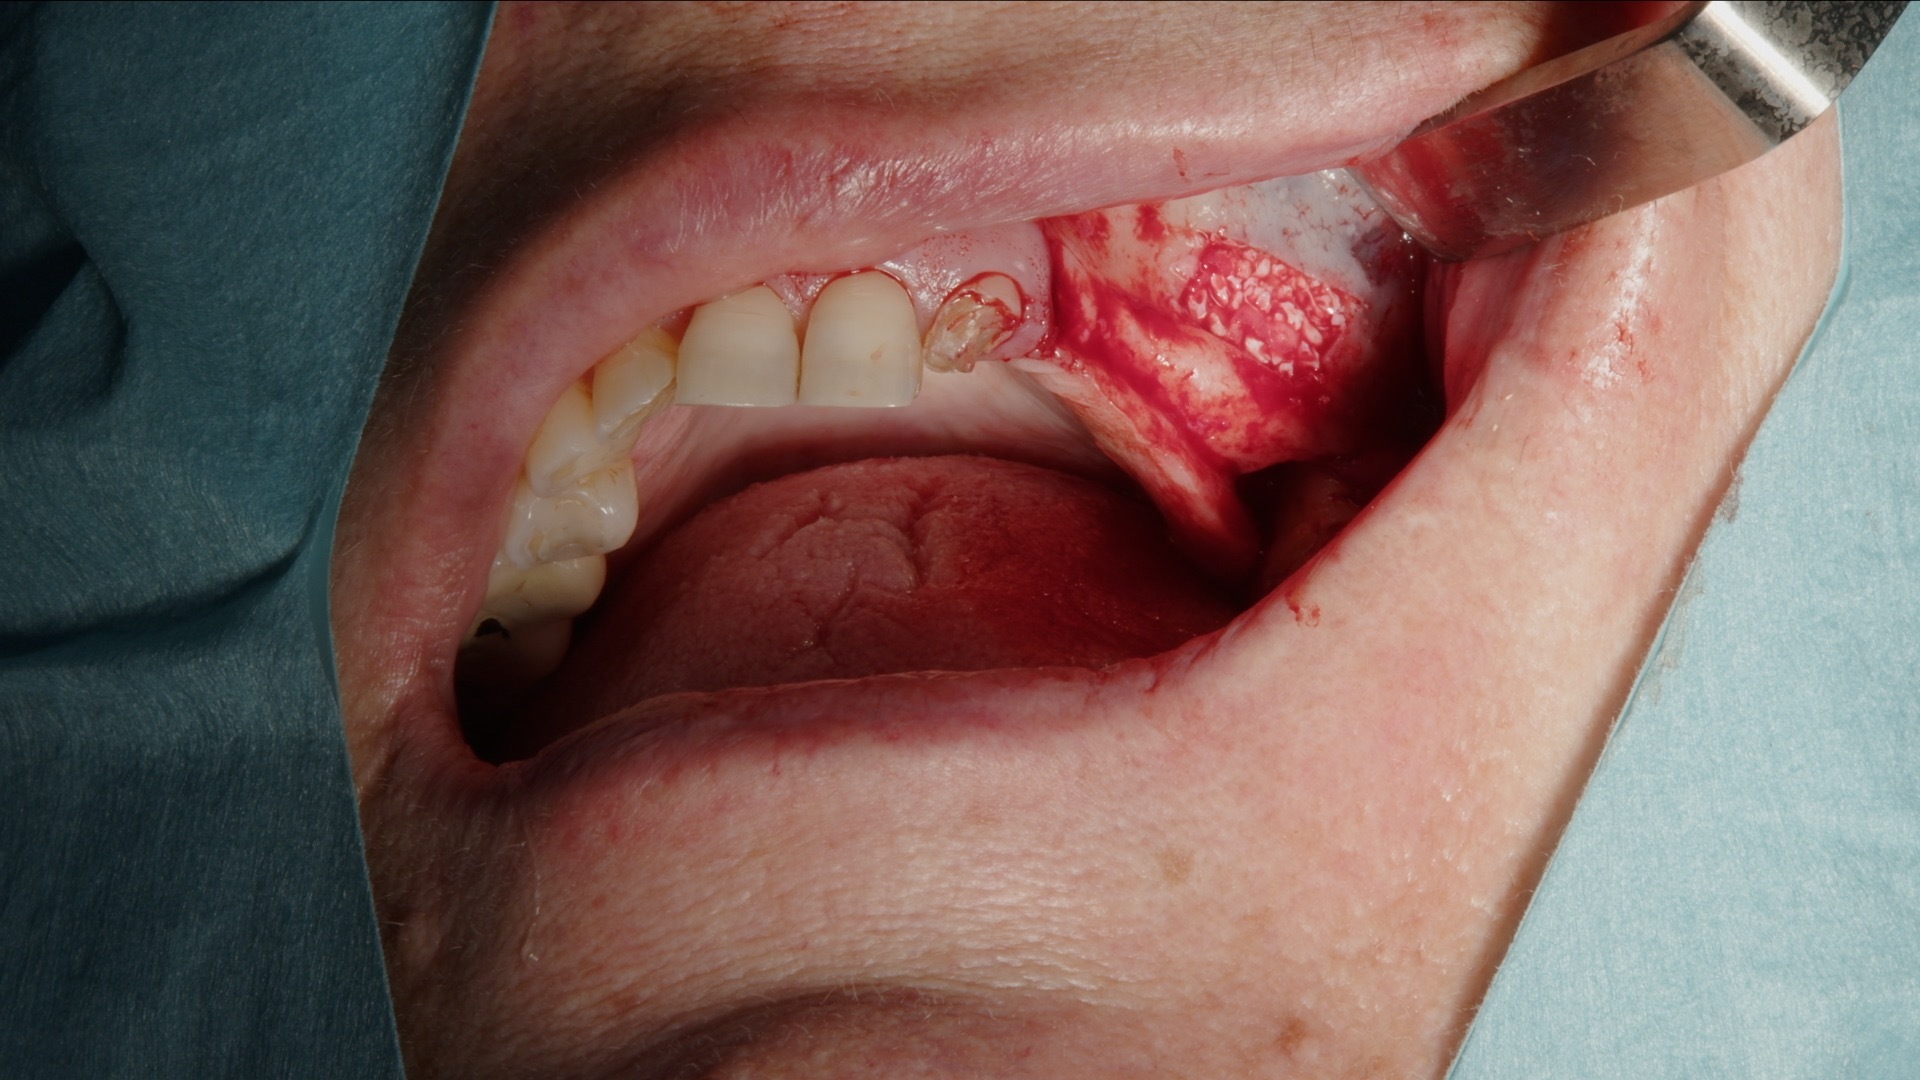

6. Fullständigt augmenterat sinusutrymme.

7. Täckning av lateralt fönster med Geistlich Bio-Gide membran.